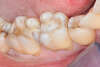

RESTAURATIONS SUR DENTS DÉVITALISÉES

Radio finale après dévitalisation de la 2ème prémolaires et de la 1ère molaire maxillaire droite (photo 1). Etant donné la faible perte de substance des dents après le traitement canalaire, des onlays en composite de laboratoire sont proposés pour reconstituer les dents. Préparation des dents dévitalisées, mise en place d’un composite en fond de cavité et sur les parois résiduelles (photo 2), prise d’empreintes. Onlays en place (photo 3), notez la bonne adaptation des bords et la morphologie restaurées des dents. Ce type de traitement permet de conserver au maximum les structures dentaires existantes.